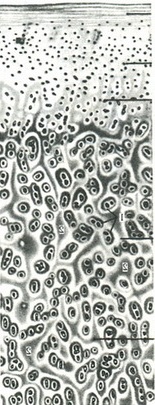

б) суглобові майданчики (facies articularis), які представляють у довгих та коротких трубчастих кісток епіфізарний кінець, оточений капсулою суглоба і перебуває в суглобовій порожнині. Суглобова майданчик у коротких кісток може розташовуватися на тілі і відростках, наприклад хребцях. Суглобові кінці мають різну форму, що і визначає в якійсь мірі характер руху в суглобі. Суглобова поверхня кожної кістки покрита суглобовим хрящем товщиною 0,25-4 мм, що мають гладку і блискучу поверхню (рис. 101). В суглобах, які несуть дуже велике навантаження, хрящ товщі. З віком спостерігається омелотворение суглобового хряща і його товщина значно зменшується;

101 Б. Схема будови суглобового хряща (за Benninghoff).

1 - хрящові клітини; 2 - пучки еластичних волокон перпендикулярного і тангенціального напрямків по відношенню до суглобової поверхні, що збільшує міцність хряща.